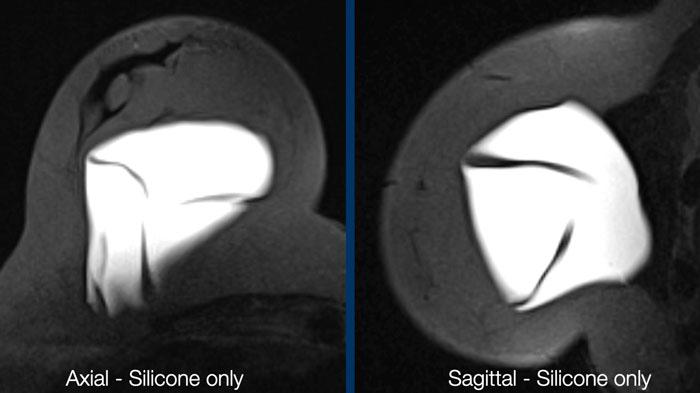

Hình ảnh chỉ hiển thị Silicone

Đây là chuỗi xung STIR, trong đó mỡ bị ức chế, kết hợp với ức chế tín hiệu nước. Kết quả là chỉ còn tín hiệu của vật liệu silicone. Chuỗi xung này lý tưởng để khảo sát tình trạng vỡ vỏ túi và phát hiện silicone nằm ngoài vỏ túi hoặc ngoài bao xơ.

Hình ảnh chỉ hiển thị nước

Sự kết hợp giữa bão hòa mỡ và ức chế silicone cung cấp thông tin về các ổ dịch tụ bên trong hoặc xung quanh túi độn.